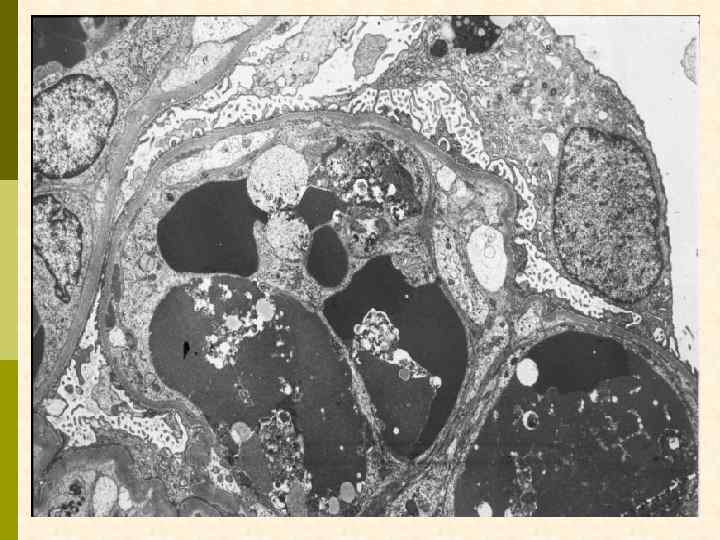

Гистологические варианты МПГН q Тип I – хроническая иммунокомплексная болезнь иммунные депозиты в мезангии и субэндотелии q нередко ассоциируется с гепатитом С, смешанной криоглобулинемией, гепатитом В, бактериальным эндокардитом q q Тип II – болезнь плотных депозитов q С 3 при иммунофлуоресценции, но без иммуноглобулинов q аутоантитела к С 3 конвертирующему ферменту (C 3 Nef) q в 90% случаев рецидивирует в трансплантате q Тип III – хроническая иммунокомплексная болезнь q в отличие от I типа имеются субэпителиальные депозиты и разрушение базальной мембраны с прозрачными лакунами

Гистологические варианты МПГН q q Тип I – хроническая иммунокомплексная болезнь q иммунные депозиты в мезангии и субэндотелии q ассоциируется с гепатитом С, смешанной криоглобулинемией, гепатитом В, бактериальным эндокардитом Тип II – болезнь плотных депозитов q q С 3 при иммунофлуоресценции, но без иммуноглобулинов аутоантитела к С 3 конвертирующему ферменту (C 3 Nef) в 90% случаев рецидивирует в трансплантате Тип III – хроническая иммунокомплексная болезнь q в отличие от I типа имеются субэпителиальные депозиты и разрушение базальной мембраны с прозрачными лакунами

Гистологические варианты МПГН q Тип I – хроническая иммунокомплексная болезнь q иммунные депозиты в мезангии и субэндотелии q ассоциируется с гепатитом С, смешанной криоглобулинемией, гепатитом В, бактериальным эндокардитом q Тип II – болезнь плотных депозитов q С 3 при иммунофлуоресценции, но без иммуноглобулинов q аутоантитела к С 3 конвертирующему ферменту (C 3 Nef) q в 90% случаев рецидивирует в трансплантате q Тип III – хроническая иммунокомплексная болезнь q в отличие от I типа имеются субэпителиальные депозиты и разрушение базальной мембраны с прозрачными лакунами